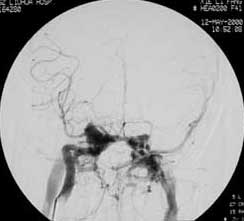

一、颅内动脉瘤

----对颅内动脉瘤的介入治疗主要分为载瘤动脉闭塞和选择性动脉瘤栓塞两种。对于颈内动脉岩部或海绵窦段以及后循环 的梭形或宽颈动脉瘤,在代偿试验良好的情况下,可以闭塞载瘤动脉。半年后动脉瘤可逐渐皱缩吸收,明显减少压迫效应 。如侧支循环代偿不足,则应先行颅内外动脉架桥。选择性动脉瘤内栓塞主要适用于瘤颈清楚、后循环动脉瘤、多次SAH、 HH分级偏高,有血管痉挛或手术风险较大的患者。 近年来,由于显微导管和栓塞材料的可控制研制,使得颅内动脉瘤的血 管内栓塞治疗越来越普遍。在欧洲,几乎占所有治疗动脉瘤的80%。栓塞材料主要由Guglielmi等发明的电解脱铂金弹簧圈 (GDC)为先导,使动脉瘤的栓塞可以控制释放弹簧圈,进出自由,大大增加了安全性和载瘤动脉的保留。经栓塞后的患者 通常2~3天即可出院。尤其对于后循环或巨大动脉瘤等手术难以接近或无法夹闭的动脉瘤,栓塞更是独辟蹊径,是手术治疗 盲区的重要补充。